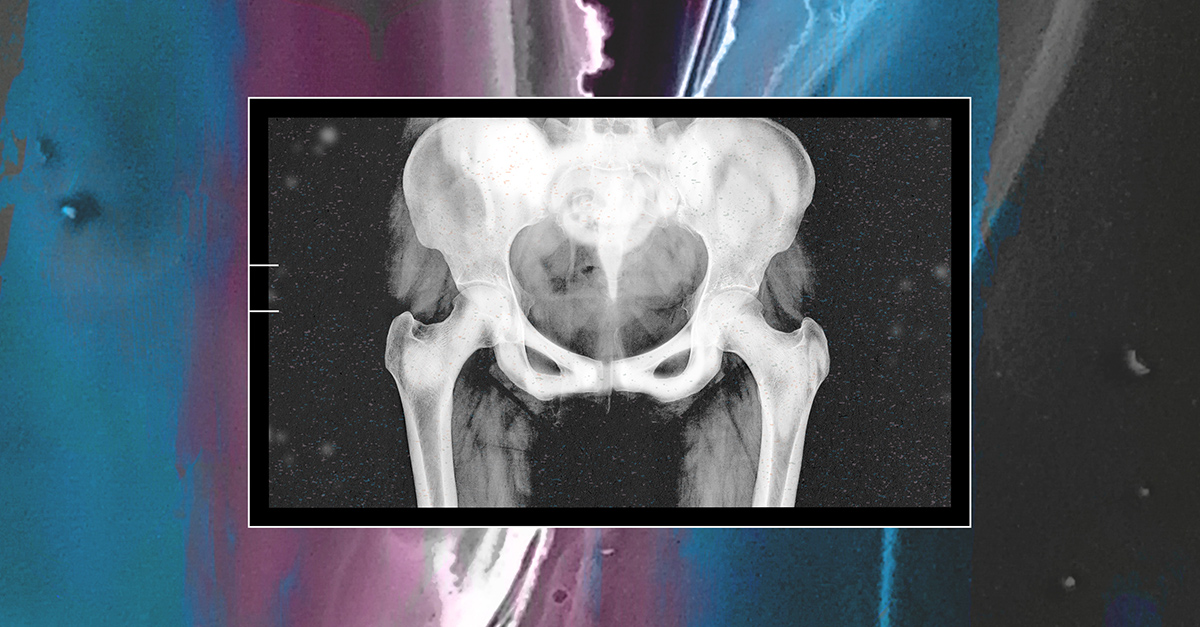

Trans women and prostate size

Another consideration is that testosterone suppression therapy shrinks the size of the prostate gland. Similar hormone therapy is often used in combination with radiation for men who have metastatic or otherwise high-risk prostate cancer to do just that.

"It makes the prostate really small, and operating to remove a really small prostate can be very difficult," Pearlman said. "It can still be irradiated, so that would probably be similar; I don't know if there's any difference for a really small prostate versus a larger one for irradiation. But then in terms of even getting a biopsy for diagnosis, it'll depend on whether they've had surgery."

The good news for a trans woman who has undergone gender-affirming bottom surgery is the prostate is relatively easy to access for a biopsy through the vagina, as the prostate sits directly up against it.